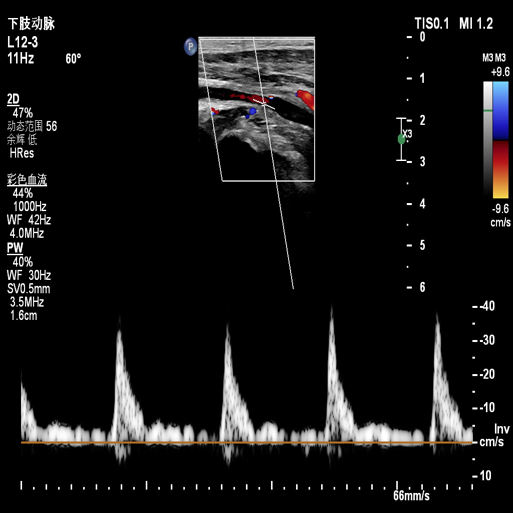

术前超声评估:提示腘动脉血栓。

图:胫腓干血栓及直径

胫后及腓动脉起始处彩色血流图